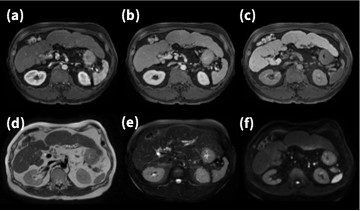

6. 最新技術を集結させた肝臓EOB検査

肝臓EOB検査では、高分解能化やDynamic studyの時間短縮化が求められるが、ARDLと圧縮センシング技術HyperSense7)がLAVAにも適用拡大されたことで、1.5T装置においても高解像度かつ短時間撮像が可能となった。 Fig.6-1に肝臓検査の一例を示す。Dynamic studyではHyperSenseを用いることで、高速化と高分解能化の両立を図り、またARDLを併用することでデノイジングと尖鋭性向上を図っている。上腹部検査では、現在ほぼ全てのシーケンスにARDLが適用されているため、旧装置に比べ検査のクオリティが格段に向上した。

また、本症例はAIR MPコイルを使用した症例であり、ハード面からも画質向上に寄与している。ここで、AIR MPコイルの特徴について述べる。

Fig.6-1 肝臓MRI画像

(a)(b)(c) : ARDL + Hyper Sense (d)(e)(f) : ARDL

(a)Dynamic 動脈相 (b) Dynamic 門脈相

(c) 肝細胞相 (d) T2 FSE (PROPELLER) _RT

(e)SSFSE_BH (f) DWI b1000_RT